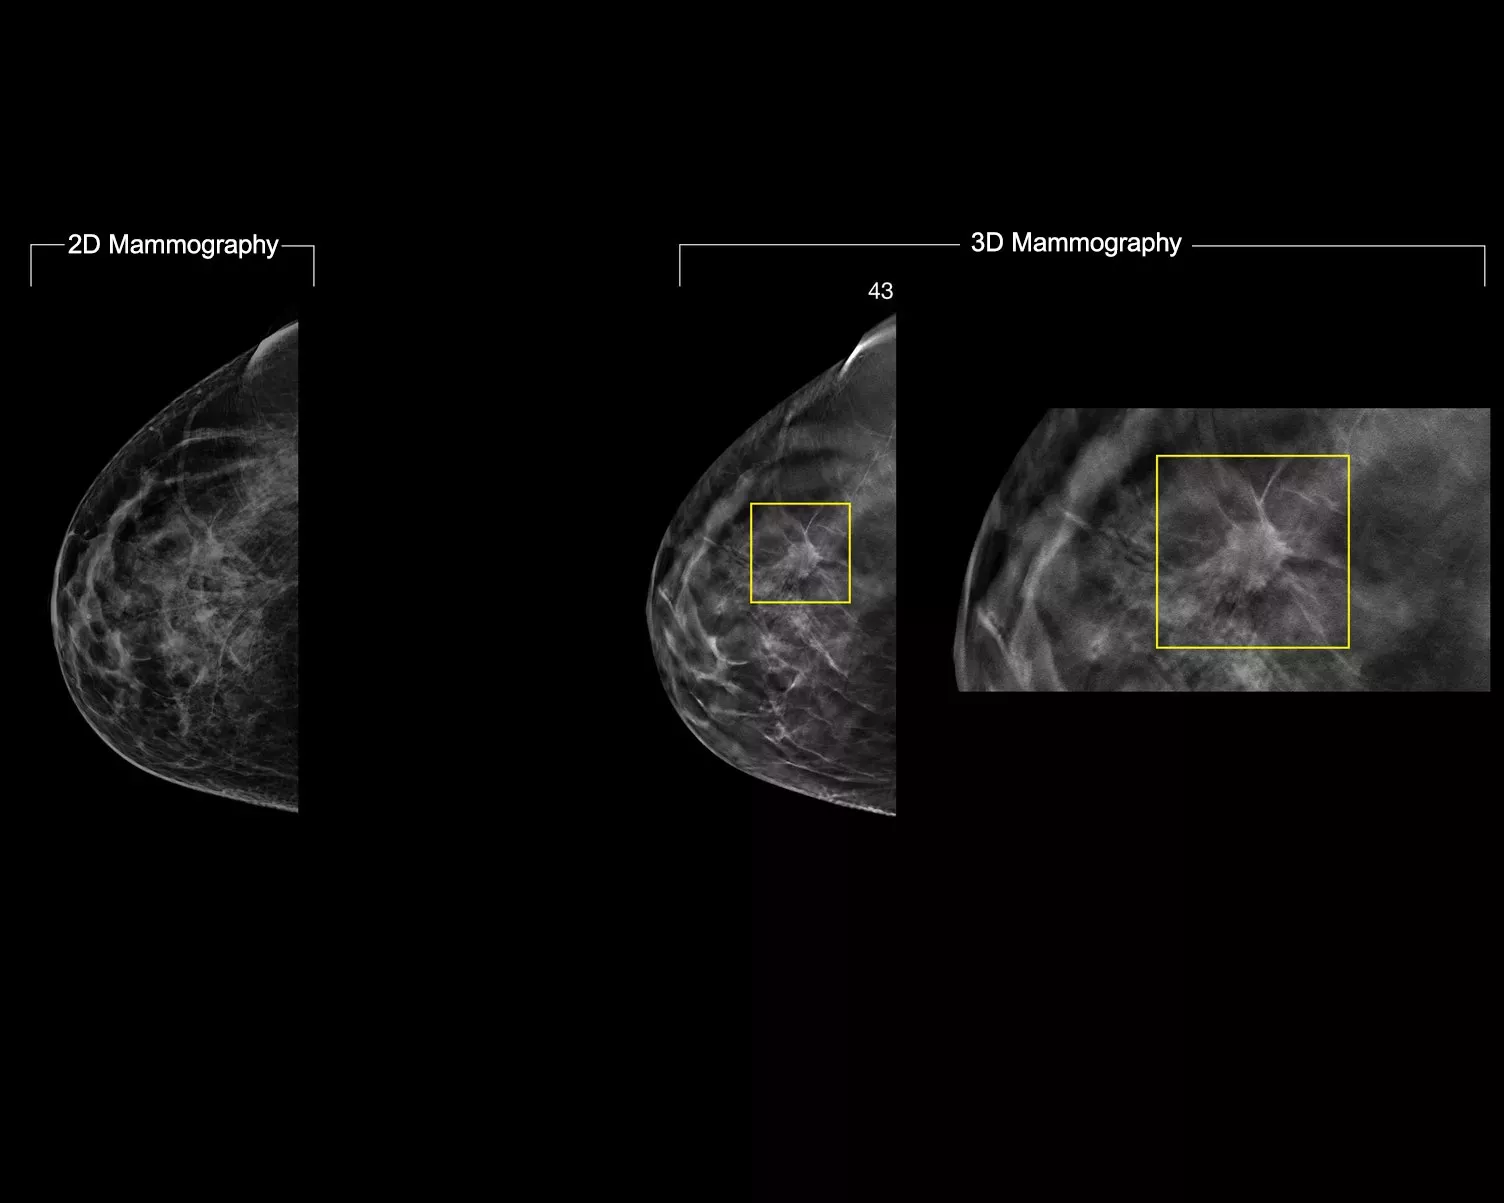

While 3D Mammography™ exams technology offer superior clinical performance compared to 2D alone,1-4 some radiologists want more: higher image quality, more detail, improved read times and low dose.

Powered by AI, Intelligent 2D imaging technology produces robust, yet natural looking, synthesised 2D images that are well correlated with the 3D mammography data. This enables radiologists to quickly and confidently see subtle mammography features and lesion morphology.*

Retain more features of interest from high-resolution 3D mammography data. Use AI-powered analytics to confidently visualise subtle tissue features and lesions in the reconstructed, synthesised 2D images.

• Exceptional 2D image contrast, sharp images with enhanced background and localised density appearance to enable FFDM-like representation of parenchymal tissue at 70μm resolution.

• Move from suspicious areas detected on the 2D image to the point of interest on the 3D mammography slice.